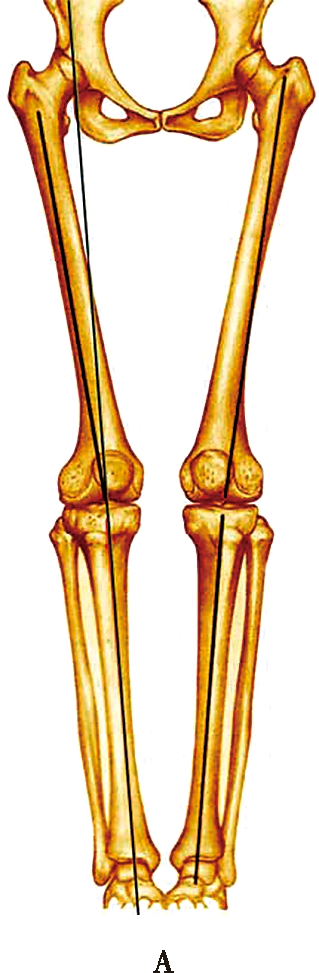

下肢力线

A:正常膝关节,下肢机械轴通过膝关节中心

B:膝内翻时,下肢机械轴位于膝关节中心内侧

下肢力线也称下肢机械轴线,即站立位X线前后像股骨头中心与踝关节中心的连线。正常人体站立时,下肢机械轴通过膝关节中心,称为“中立”力学轴线。此时,股骨解剖轴与下肢力线有平均6°的外翻角;胫骨解剖轴与机械力线重合。在病理情况下,由于膝关节内翻或外翻,下肢的机械轴将会偏离膝关节的中心。膝内翻时下肢机械轴位于膝关节中心内侧,膝外翻时下肢机械轴位于膝关节中心外侧。膝关节置换术后,股骨假体通常有5°~7°的外翻,现代胫骨假体的设计在冠状面上通常与机械轴垂直,这对于重建“中立”力学轴线是至关重要的